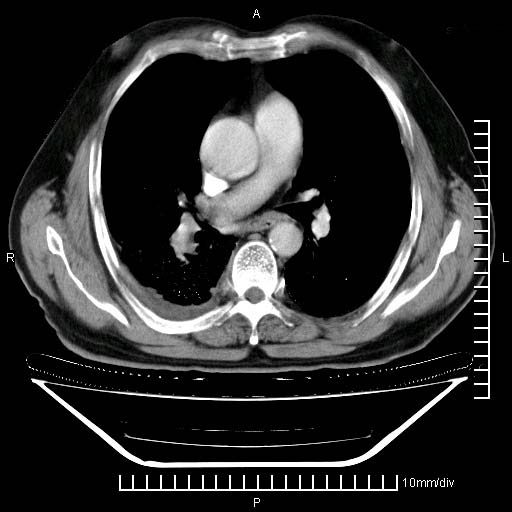

既往肺结核,近10几天,咳嗽,咳痰,右侧胸痛,疼痛较明显,右上肺斑块考虑结核灶胸膜粘连,增强,可惜动脉期没有定好,未见强化,可延迟4分后又见较明显强化,中心见低密度影,如果说结核是边缘强化,可这个灶强化的面积挺大的,让人很挠头。

1)两肺继发性肺结核。2)右侧胸膜增厚+少量胸腔积液。